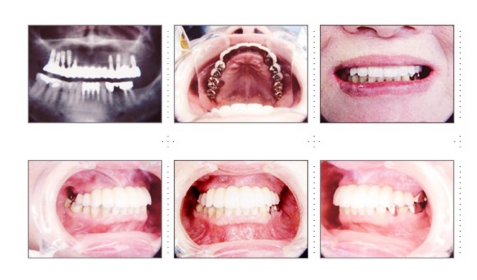

症例5

62才 女性

老舗の有名蕎麦屋さんの店主の方で、長年歯では苦労されておりました。口腔内写真は術中です。初めて来院されたときには、日常生活にも不便な状態でしたので、術前の口腔内写真を撮るより先に、治療を始めました。下顎は両側犬歯を残し、他は抜歯。インプラント7本埋入。 遠方からの方なので、集中治療を行いインプラント14本埋入し、上下顎共に、セラミック(MB)クラウンにしました。「歯は女優さん並になりました。」 と大変喜んで頂きました。